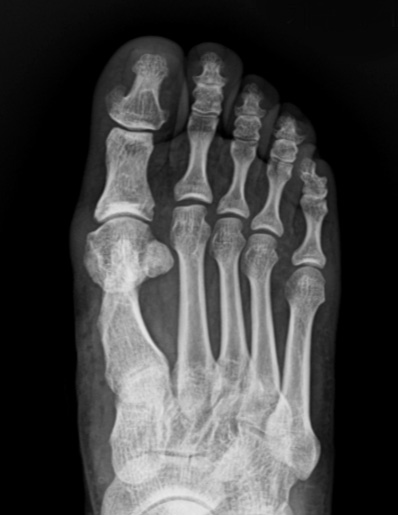

기구제거 후

수술 후에는 관절이 잘 맞아 들어간 것을 확인할 수 있습니다.

* 환자에게 받은 소중한 자료입니다.